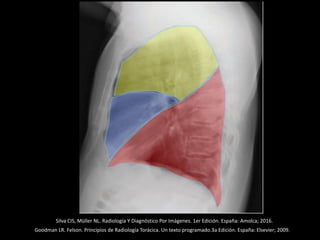

Silva CIS, Müller NL. Radiología Y Diagnóstico Por Imágenes. 1er Edición. España: Amolca; 2016.

Divisiones del mediastino:

Anatómica (Gray) y Radiológica (Felson)

SUPERIOR

• Aorta

• Grandes vasos

• Tráquea

• Tercio superior del esófago

• Timo superior

• Ganglios linfáticos (GL)

ANTERIOR MEDIO POSTERIOR

• Grasa

mediastinal

• Timo

• GL

• Pericardio

y

contenido

• Carina

• Esófago

torácica

descendente

• Vena ácigos

• Conducto

torácico

ANTERIOR MEDIO POST

Gray

Felson

Radiology: Vol. 272: No. 1—July 2014

Felson B. Chest roentgenology. Philadelphia: W.B. Saun-ders; 1973.